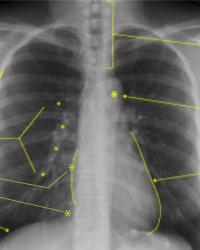

Figure - 01

CXR Sweet Spot™ Box Measurements |